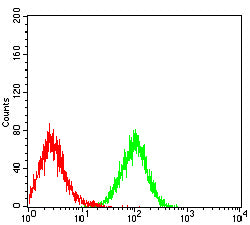

分类: 科研抗体货号: 31977别名: LeX; CD15; ELFT; FCT3A; FUTIV; SSEA-1; FUC-TIV应用: FCM反应种属: Human